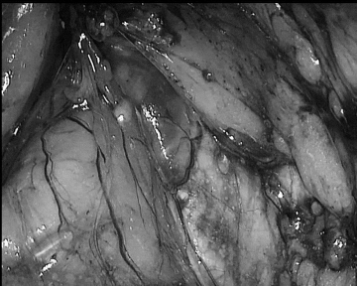

▲ 图2 切开双侧盆底筋膜、离断前列腺侧血管蒂及阴茎神经血管束